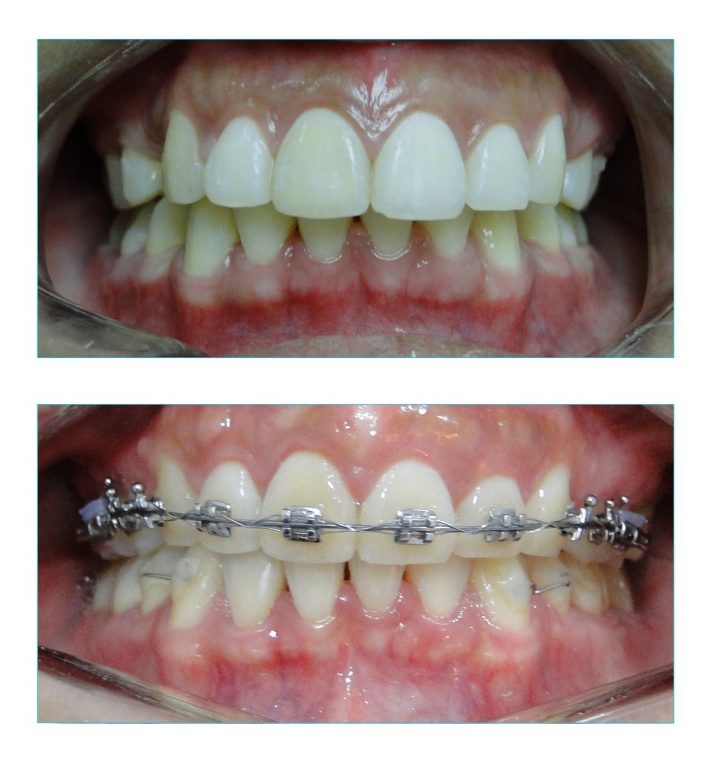

O caso mostrado aqui foi iniciado por outro profissional que indicou as extrações.

Porém, em certo ponto do tratamento, os espaços pararam de fechar. Por mais que se aumentasse a força aplicada, os dentes já não respondiam com movimentação.

Esse efeito é muito comum, principalmente em casos com quatro extrações de pré-molares em que não havia muita falta de espaço nas arcadas.

Ou seja, os tratamentos de biprotursão, são os que apresentam maior risco de fechamento incompleto dos espaços.

A paciente chegou com essas separações e foi muito difícil conseguir o fechar completamente os espaços.

Esse caso foi muito difícil, pois foi iniciado de forma errada por outro profissional, que no meio do tratamento já não conseguia mais fechar o espaço. Tive que desfazer tudo e levei quase dois anos para fechar completamente os espaços.

Ainda assim, mantenho essa paciente (e todos os outros também) monitorando anualmente a estabilidade do caso.

Porque tem aquela borrachinha roxa em cima da banda?

Oi Amanda!

Isso é uma ligadura elástica igual a que usamos para prender o arco no bracket.

Nesse caso ela está sendo usada para fixar o arco à ultima peça do aparelho (o Tubo) e evitar que os espaços das extrações abram de novo.

Nesse caso, a paciente chegou para mim já com os dentes extraídos e o ortodontista dela não conseguia fechar os espaços. Deu um trabalhão, mas consegui.